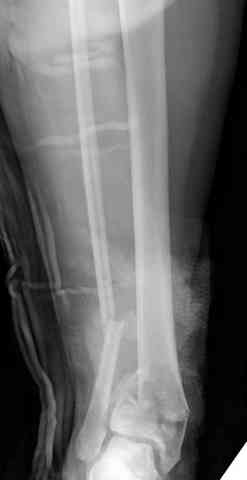

Переломы пилона сопровождаются ударом со сминанием в метафизарной части большеберцовой, то есть со значительной потерей костного объема.

При репозиции суставных поверхностей образуются полости в метафизарных отделах, без заполнения их

структуральными элементами невозможно предохраниться от посттравматической деформации. Латеральная колонна удерживается малоберцовой поэтому голень деформируется в варус.

Аутокость является самым надежным материалом, но при желании можно применить синтетический заполнитель Osteoset Pallets - структуральный материал, по аннотации материал через определенное время интегрируется в кость.

Здесь выставлена пара случаев перелома пилона, оба

случая леченные этапным наружным фиксатором.